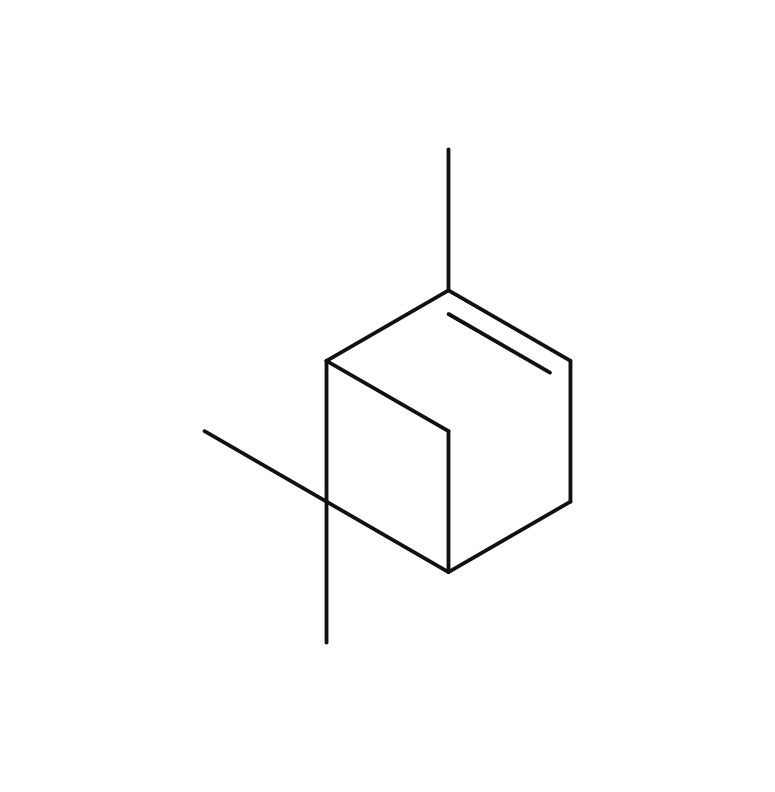

抗炎症 (Anti-inflammatory Effects)

消臭 (Deodorizing Effects)

抗マラリア (Anti-malaria Effects)

抗酸化 (Anti-oxidant Effects)

平滑筋の緊張緩和 (Smooth Muscle Relaxation)

作業能率の向上 (Work efficiency Improvement)